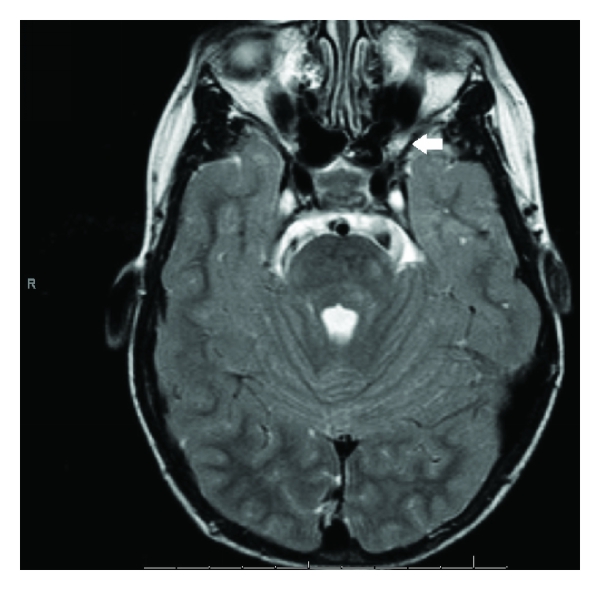

Currently, he is eight years old and is clinically well and asymptomatic. Nevertheless, cranial magnetic resonance imaging revealed a left optic nerve glioma in its prechiasmatic segment (Figure 1). After evaluation by a multidisciplinary team, it was decided to pursue a conservative approach with regular clinical and neuroimagiological followups (at 3 to 12 months intervals). There is no tumor progression until now in our patient.